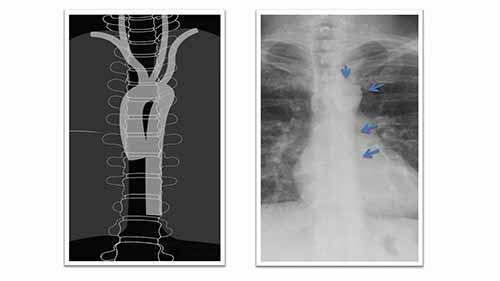

外科影像市场

简介:我们将从技术、应用和终端用户等方面,来分析2022年的外科影像市场以及2029年的发展趋势。

了解胸部X光——形状的重要性

在今天的教学视频中,你将了解气管,主动脉,心脏等组织在胸部X光片上呈现出什么形状。

了解胸部X光——重叠的重要性

如果你想看懂胸部X光片,你需要知道胸腔中不同的解剖结构如何相互作用来创建影像。